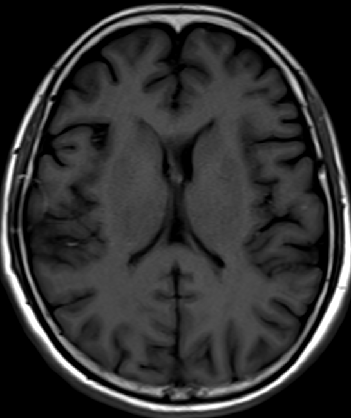

2013-5-16

2013-8-2

2014-12-13

2015-4-1